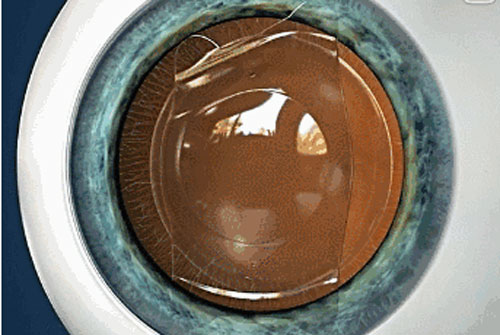

ICL晶體植入手術無需切削角膜組織,而是將小小的“眼鏡”植入眼內,具有可逆性,適合近視1800度以內、散光600度以內的高度近視者,還可一次性解決散光、遠視、老花等問題。